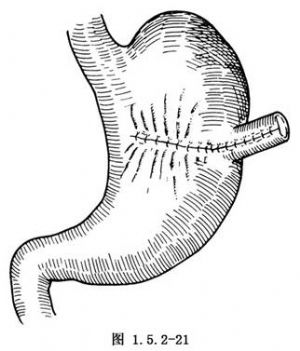

再用细的不吸收线做一层浆肌层间断缝合(图1.5.2-21)。